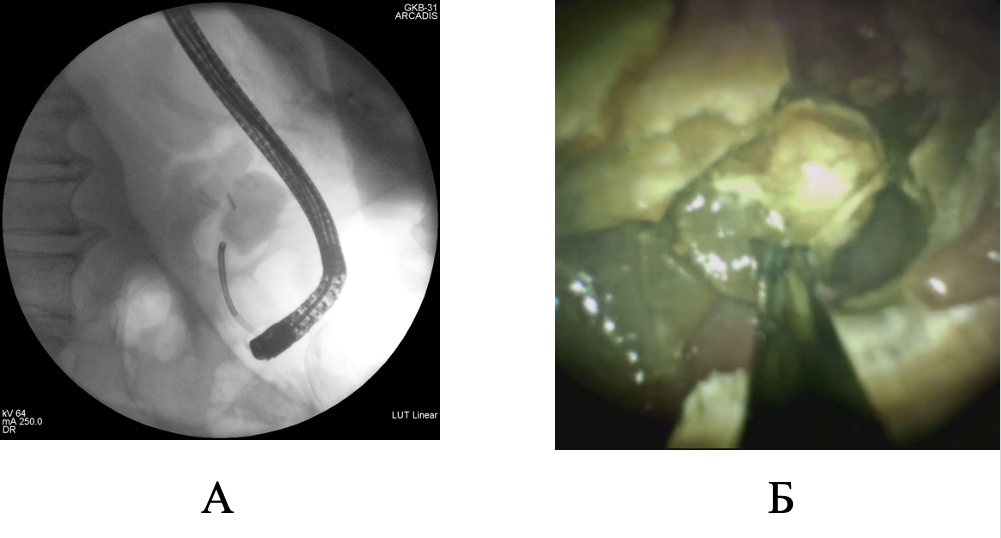

Представлено клиническое наблюдение успешного этапного эндоскопического лечения при гигантском множественном холедохолитиазе. Традиционное хирургическое вмешательство было противопоказано пациентке ввиду выраженных сопутствующих заболеваний и большого анестезиологического риска. Базовым методом мини-инвазивного лечения была контактная литотрипсия, дополненная баллонной дилатацией зоны эндоскопической папиллосфинктеротомии и механической внутрипротоковой литотрипсией. Применение контактной литотрипсии при пероральной транспапиллярной холангиоскопии в сочетании с другими современными способами эндоскопического лечения холедохолитиаза обладает хорошим техническим и клиническим эффектом даже при гигантских размерах билиарных конкрементов.